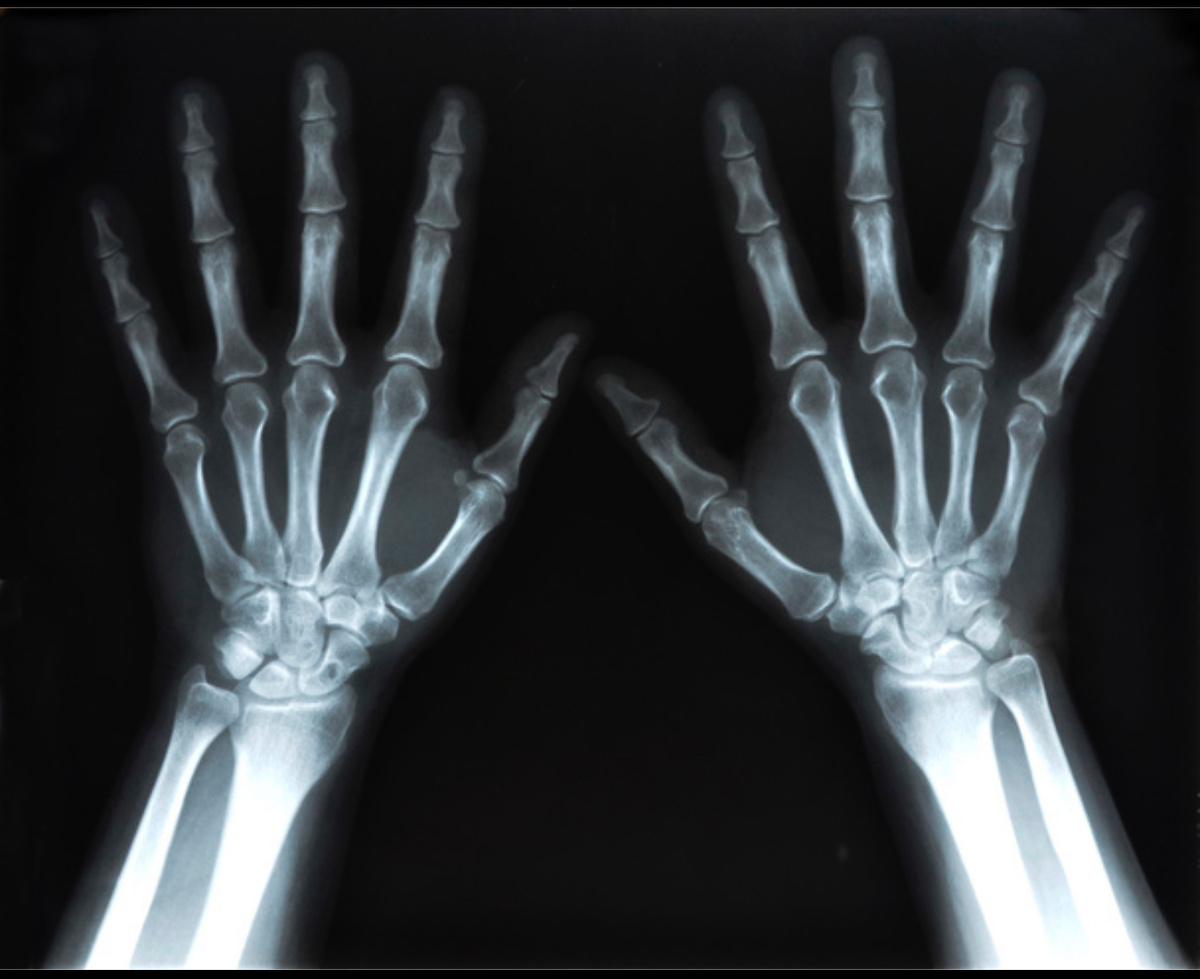

Один из наиболее частых случаев — контроль заживления переломов костей. Так, после перелома конечности, рентгенография помогает точно определить положение костных отломков и оценить степень сращения кости. Это особенно важно в первые месяцы реабилитации, чтобы своевременно скорректировать методы иммобилизации и физической нагрузки. Если увидеть смещение или несращение, врач может изменить лечение или рекомендовать оперативное вмешательство.

Еще один пример — использование рентгена для диагностики и контроля заболеваний позвоночника. При сколиозе или остеохондрозе рентген помогает увидеть степень искривления, состояние межпозвонковых дисков и костных структур. Это позволяет врачу определить, какие методы ЛФК, массажей и физиотерапии будут наиболее эффективными, а также контролировать динамику исправления позвоночника во время курса реабилитации. Аналогично, при травмах и воспалениях суставов рентгенография выявляет вывихи, подвывихи, артрозные изменения и помогает скорректировать нагрузки и поддерживающие процедуры.

В ряде случаев рентген используется в сочетании с терапевтическим облучением (рентгенотерапией), что помогает уменьшить воспаление и боль при хронических артритах и других дистрофических заболеваниях суставов, ускоряя выздоровление и улучшая качество жизни пациента